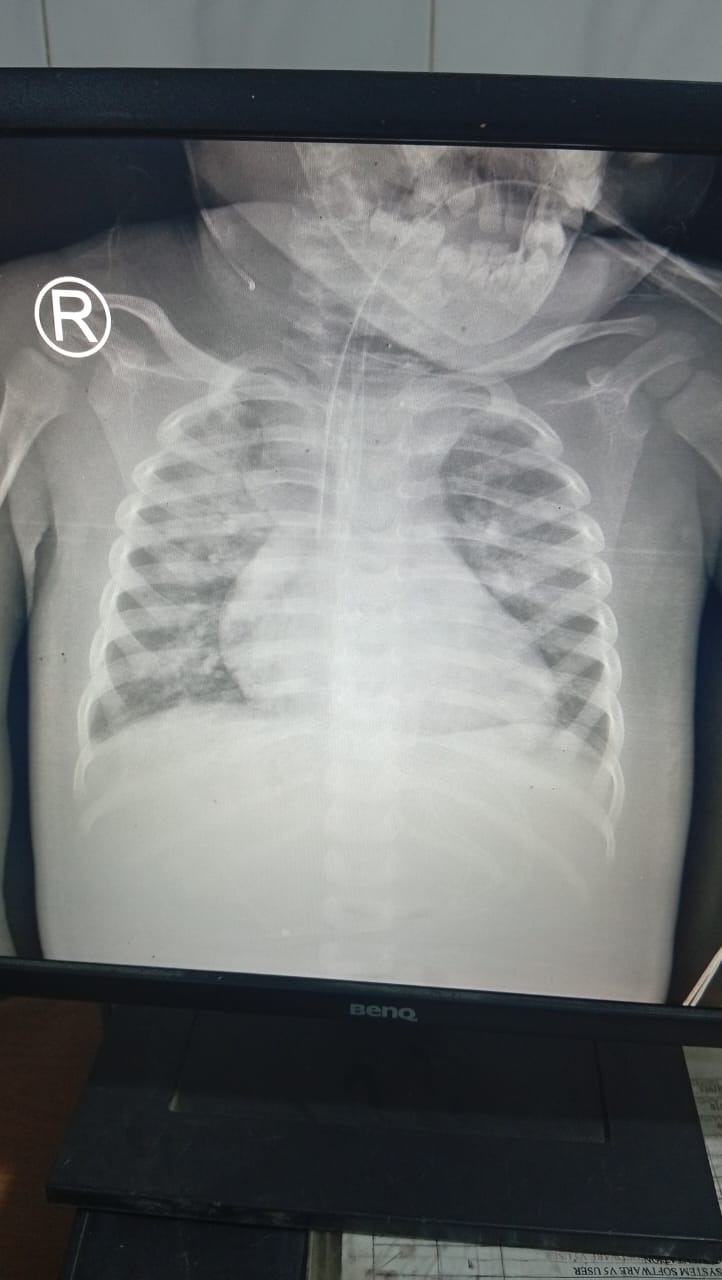

ووفقًا لما أكدته الأسرة، يعاني الطفل من مضاعفات صحية خطيرة تتمثل في عدم قدرته على الوقوف على قدميه، إلى جانب وجود بلغم كثيف بالصدر، واضطراب في ضغط الدم، فضلًا عن استمرار وجود ميكروب لم تستجب حالته للعلاج حتى الآن، بحسب نتائج التحاليل الطبية.

وأوضحت الأسرة أن الأطباء المشرفين على الحالة أكدوا تعقيد الوضع الصحي، مما يستدعي عرض الطفل بشكل عاجل على استشاري مخ وأعصاب لتقييم سبب عدم القدرة على الوقوف، إضافة إلى استشاري باطنة لمتابعة اضطراب الضغط والحالة العامة، وكذلك تدخل فريق علاج طبيعي متخصص للحفاظ على كفاءة العضلات ومنع حدوث مضاعفات إضافية نتيجة طول فترة البقاء في العناية المركزة.